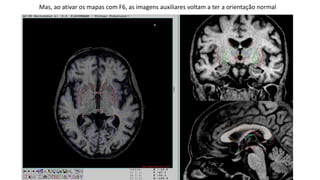

Mas, ao ativar os mapas com F6, as imagens auxiliares voltam a ter a orientação normal

Mas, ao ativaros mapas com F6, as imagens auxiliares voltam a ter a orientação normal